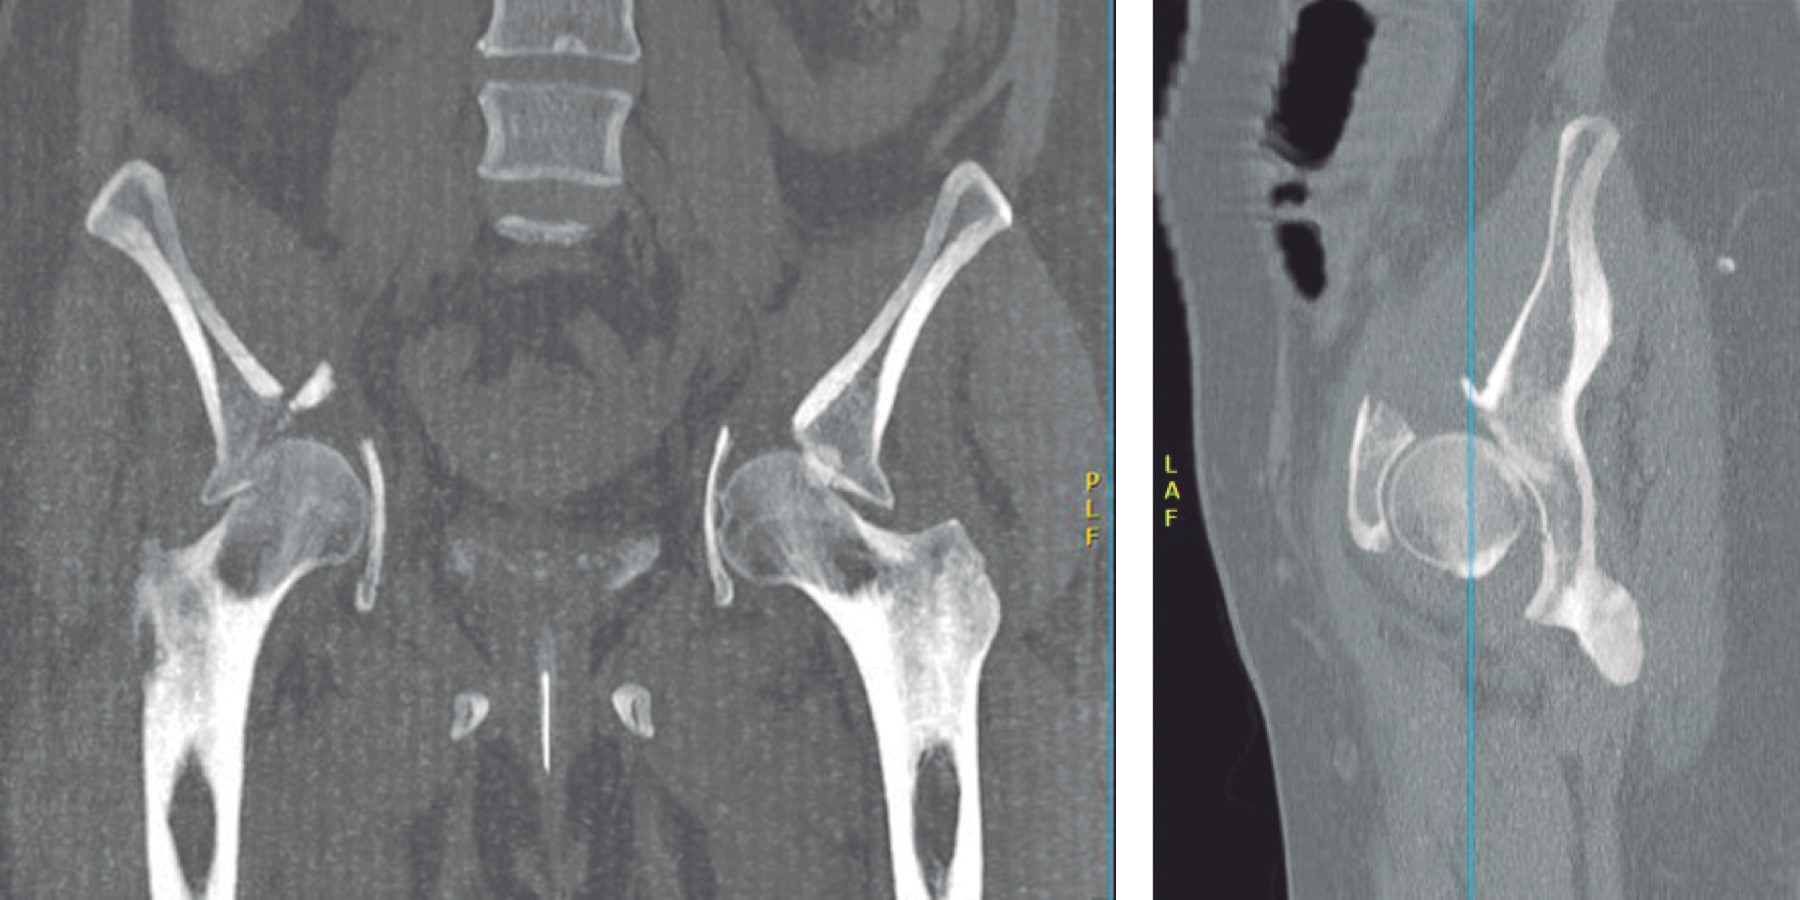

Bilateral acetabular fracture secondary to seizure. Case report and literature review

Introduction: acetabular fractures are generally related to high energy mechanisms. A case report and literature review are exposed. There are few publications with reports of bilateral acetabular fractures secondary to seizures, a total of 26 case reports, no citations in the Mexican population. Objective: to present a case of bilateral fracture of the acetabulum associated with convulsive crises, its management and clinical evolution. As well as a review of the literature and injury mechanims. Clinical case: a 68-year-old female patient who debuted with an episode of seizures, presenting with a bilateral fracture of the AO acetabulum type 62B3.3/Judet, I. Performing surgical management, through open reduction and internal fixation using a modified Stoppa approach with two plates. 9-hole curved reconstruction plates for the left acetabulum and one open reduction and internal fixation with two 10-hole reconstruction plates and one 6-hole spring plate for the right acetabulum, presenting excellent functional results. Conclusion: the injury mechanims of acetabular fractures continues to be of high energy, with few cases associated with seizures reported in the literature. Inevitably the patient will evolve to a post-traumatic coxarthrosis; the initial management with osteosynthesis and acetabular reconstruction is focused on the future definitive treatment with bilateral total hip arthroplasty with primary components, so far the result is encouraging.

Figure 3